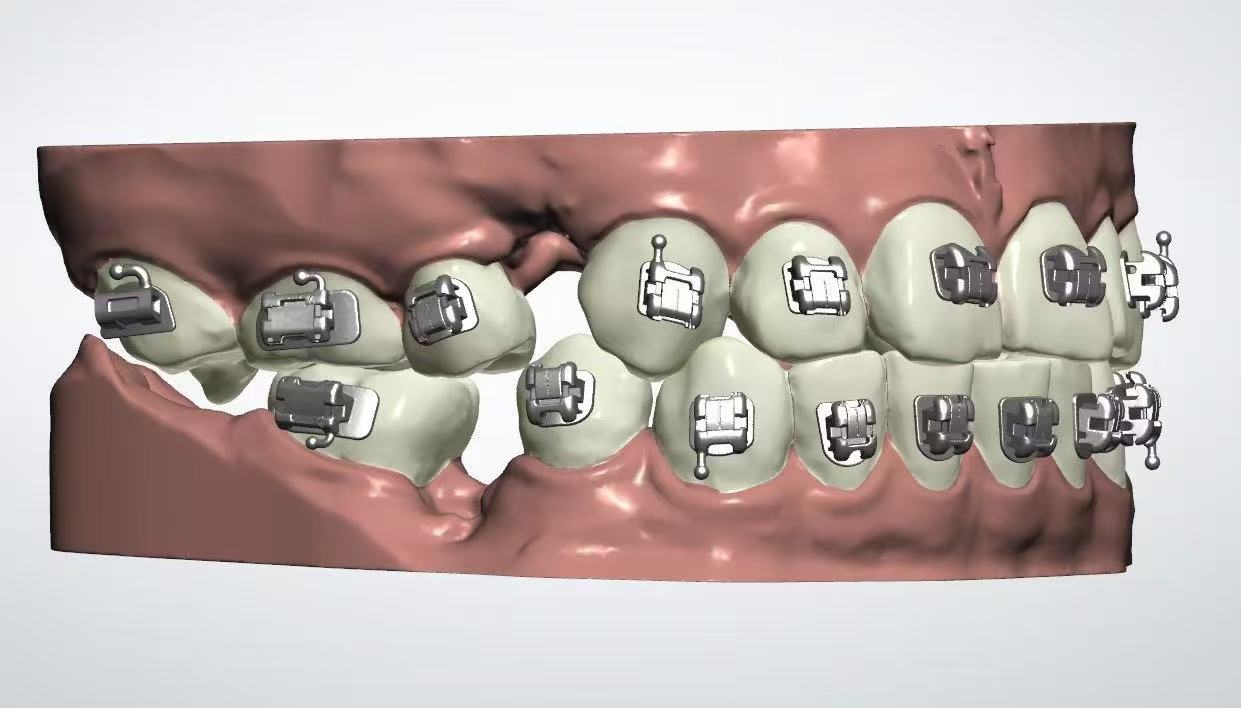

真实案例

TRUE CASE